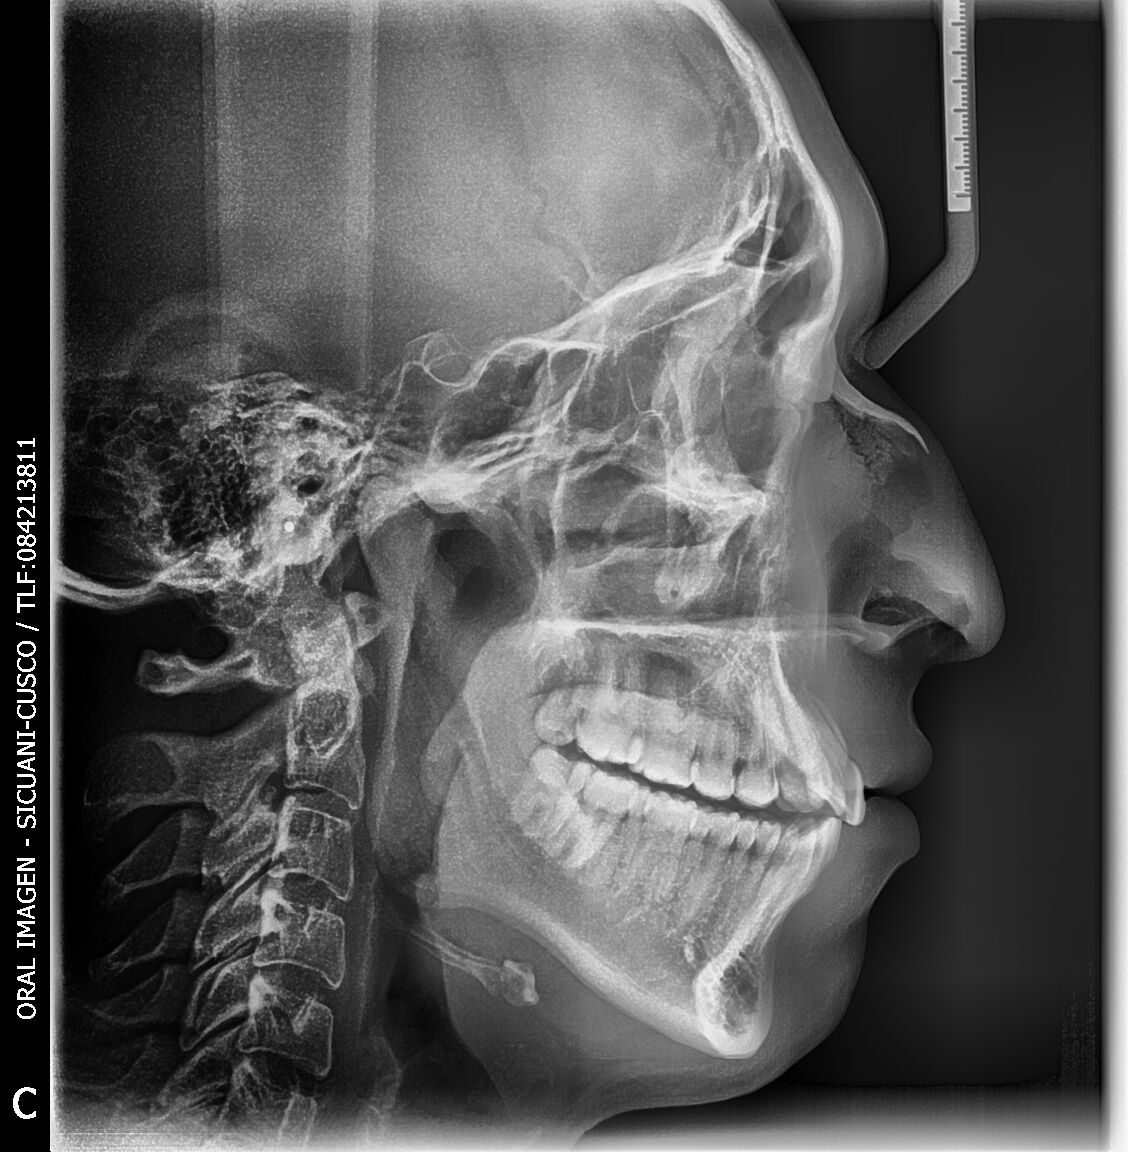

Gracias al Dr. JOSE TAYA MIRANDA, por confiar en nosotros y haber adquirido el paquete completo. Centro de diagnosticos, ubicado en la Av. Manuel Callo 457 - Sicuani-Cusco, instalación de equipo PaX-iSC (Panorámico-Cefalometrico),EzSensor Classic y EzRay Air de la marca VATECH.